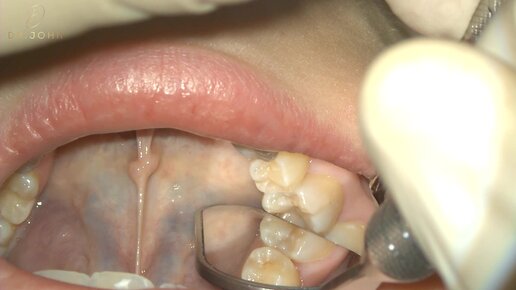

Лечение скрытого кариеса, нижний моляр